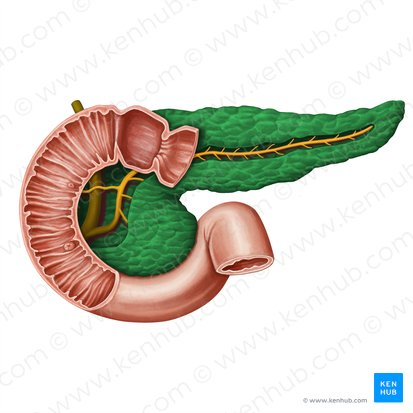

Pancreas

A gland located behind the stomach that produces digestive enzymes and hormones like insulin and glucagon.

Pancreatic Duct

A duct that carries digestive enzymes produced by the pancreas to the duodenum. It typically joins with the bile duct before entering the duodenum.

Pancreatic Duct / Duct of Wirsung

The main duct that runs through the length of the pancreas, collecting digestive enzymes from the pancreatic cells and transporting them to the duodenum.

Accessory Pancreatic Duct / Duct of Santorini

A smaller pancreatic duct that branches off the main pancreatic duct and may also empty into the duodenum, usually superior to the major duodenal papilla.

Hepatopancreatic Ampulla / Ampulla of Vater

A dilated chamber formed by the joining of the common bile duct and the pancreatic duct before they enter the duodenum.

Sphincter of Hepatopancreatic Ampulla / Sphincter of Oddi

A muscular valve that surrounds the hepatopancreatic ampulla and controls the flow of bile and pancreatic juice into the duodenum.

Major Duodenal Papilla

The raised opening in the wall of the duodenum where the hepatopancreatic ampulla typically empties its contents.

Mucosa of Duodenum

The inner lining of the duodenum, which contains specialized cells for absorption and secretion.

Duodenum

This is the first and shortest segment of the small intestine. It receives partially digested food (known as chyme).

Receives digestive enzymes from the pancreas and bile from the liver and gallbladder through the pancreatic and bile ducts.

Major Duodenal Papilla

An opening in the wall of the duodenum where the common bile duct and the pancreatic duct typically enter to deliver bile and pancreatic enzymes.